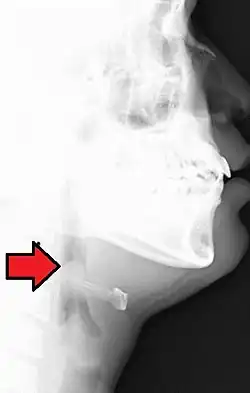

| Lateral radiograph showing the "thumb sign". The diagnosis of epiglottitis was confirmed on subsequent imaging and laryngoscopy. The patient recovered following treatment with prednisone and ceftriaxone | |

| Differential diagnosis | epiglottitis or intestinal ischemia |

In radiology, the thumbprint sign, or thumbprinting, is a radiologic sign found on a radiograph that suggests the diagnosis of either epiglottitis or intestinal ischemia.

In a lateral C-spine radiograph, the sign is caused by a thickened free edge of the epiglottis, which causes it to appear more radiopaque than normal, resembling the distal thumb.